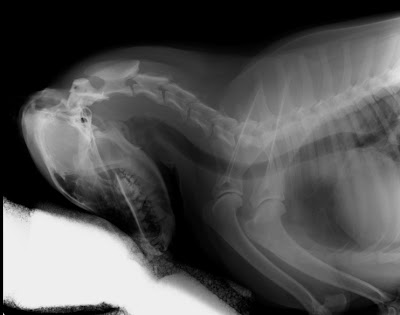

Pani mówi, że zasadniczo kości mam podobne do tych człowiekowych. Ciekawostka dla tych którzy nie wiedzą, wszystkie ssaki od myszki przez ludzi po żyrafę czy słonia mają siedem kręgów szyjnych. Matka natura potrafi być niesamowita :)

Pani doktor od rehabilitacji powiedziała, że wszystkie moje objawy świadczą o tym, że mam uraz odcinka szyjnego. Tak więc dogipsowała mnie po same uszy :( teraz jak się położę na boku to ledwo wstaję bo tak mam usztywnioną szyję.

Jeżeli nie miałbym tego usztywnienia to byłaby duża szansa na poważniejszy uraz wiążący się nawet z paraliżem przednich łapek.

To co mi dolega to coś w rodzaju wcześnie wykrytej przepukliny kręgosłupa. Wcześnie wykrytej, tzn jeszcze nieoperacyjnej, a dającej się wyleczyć właśnie za pomocą usztywnienia oraz rehabilitacji.

Patrząc na obrazek na którym namalowany jest kręgosłup to mnie dotyczy faza początkowa. Właśnie dlatego mam gips, żeby usztywnić szyję. Dzięki temu, że nie mam jak nią poruszać ustrojstwa zwane makrofagami odbudowują to co się zepsuło w mojej szyi – niestety trwa to trzy tygodnie. Żeby przyspieszyć cały proces regeneracji mam zabiegi zwane magnetoterapią (inaczej pole magnetyczne). To akurat już jest całkiem spoko, bo leżę tylko przez 30 minut :)

![]() |

| W nowym namordniku :) jest całkiem znośny. |